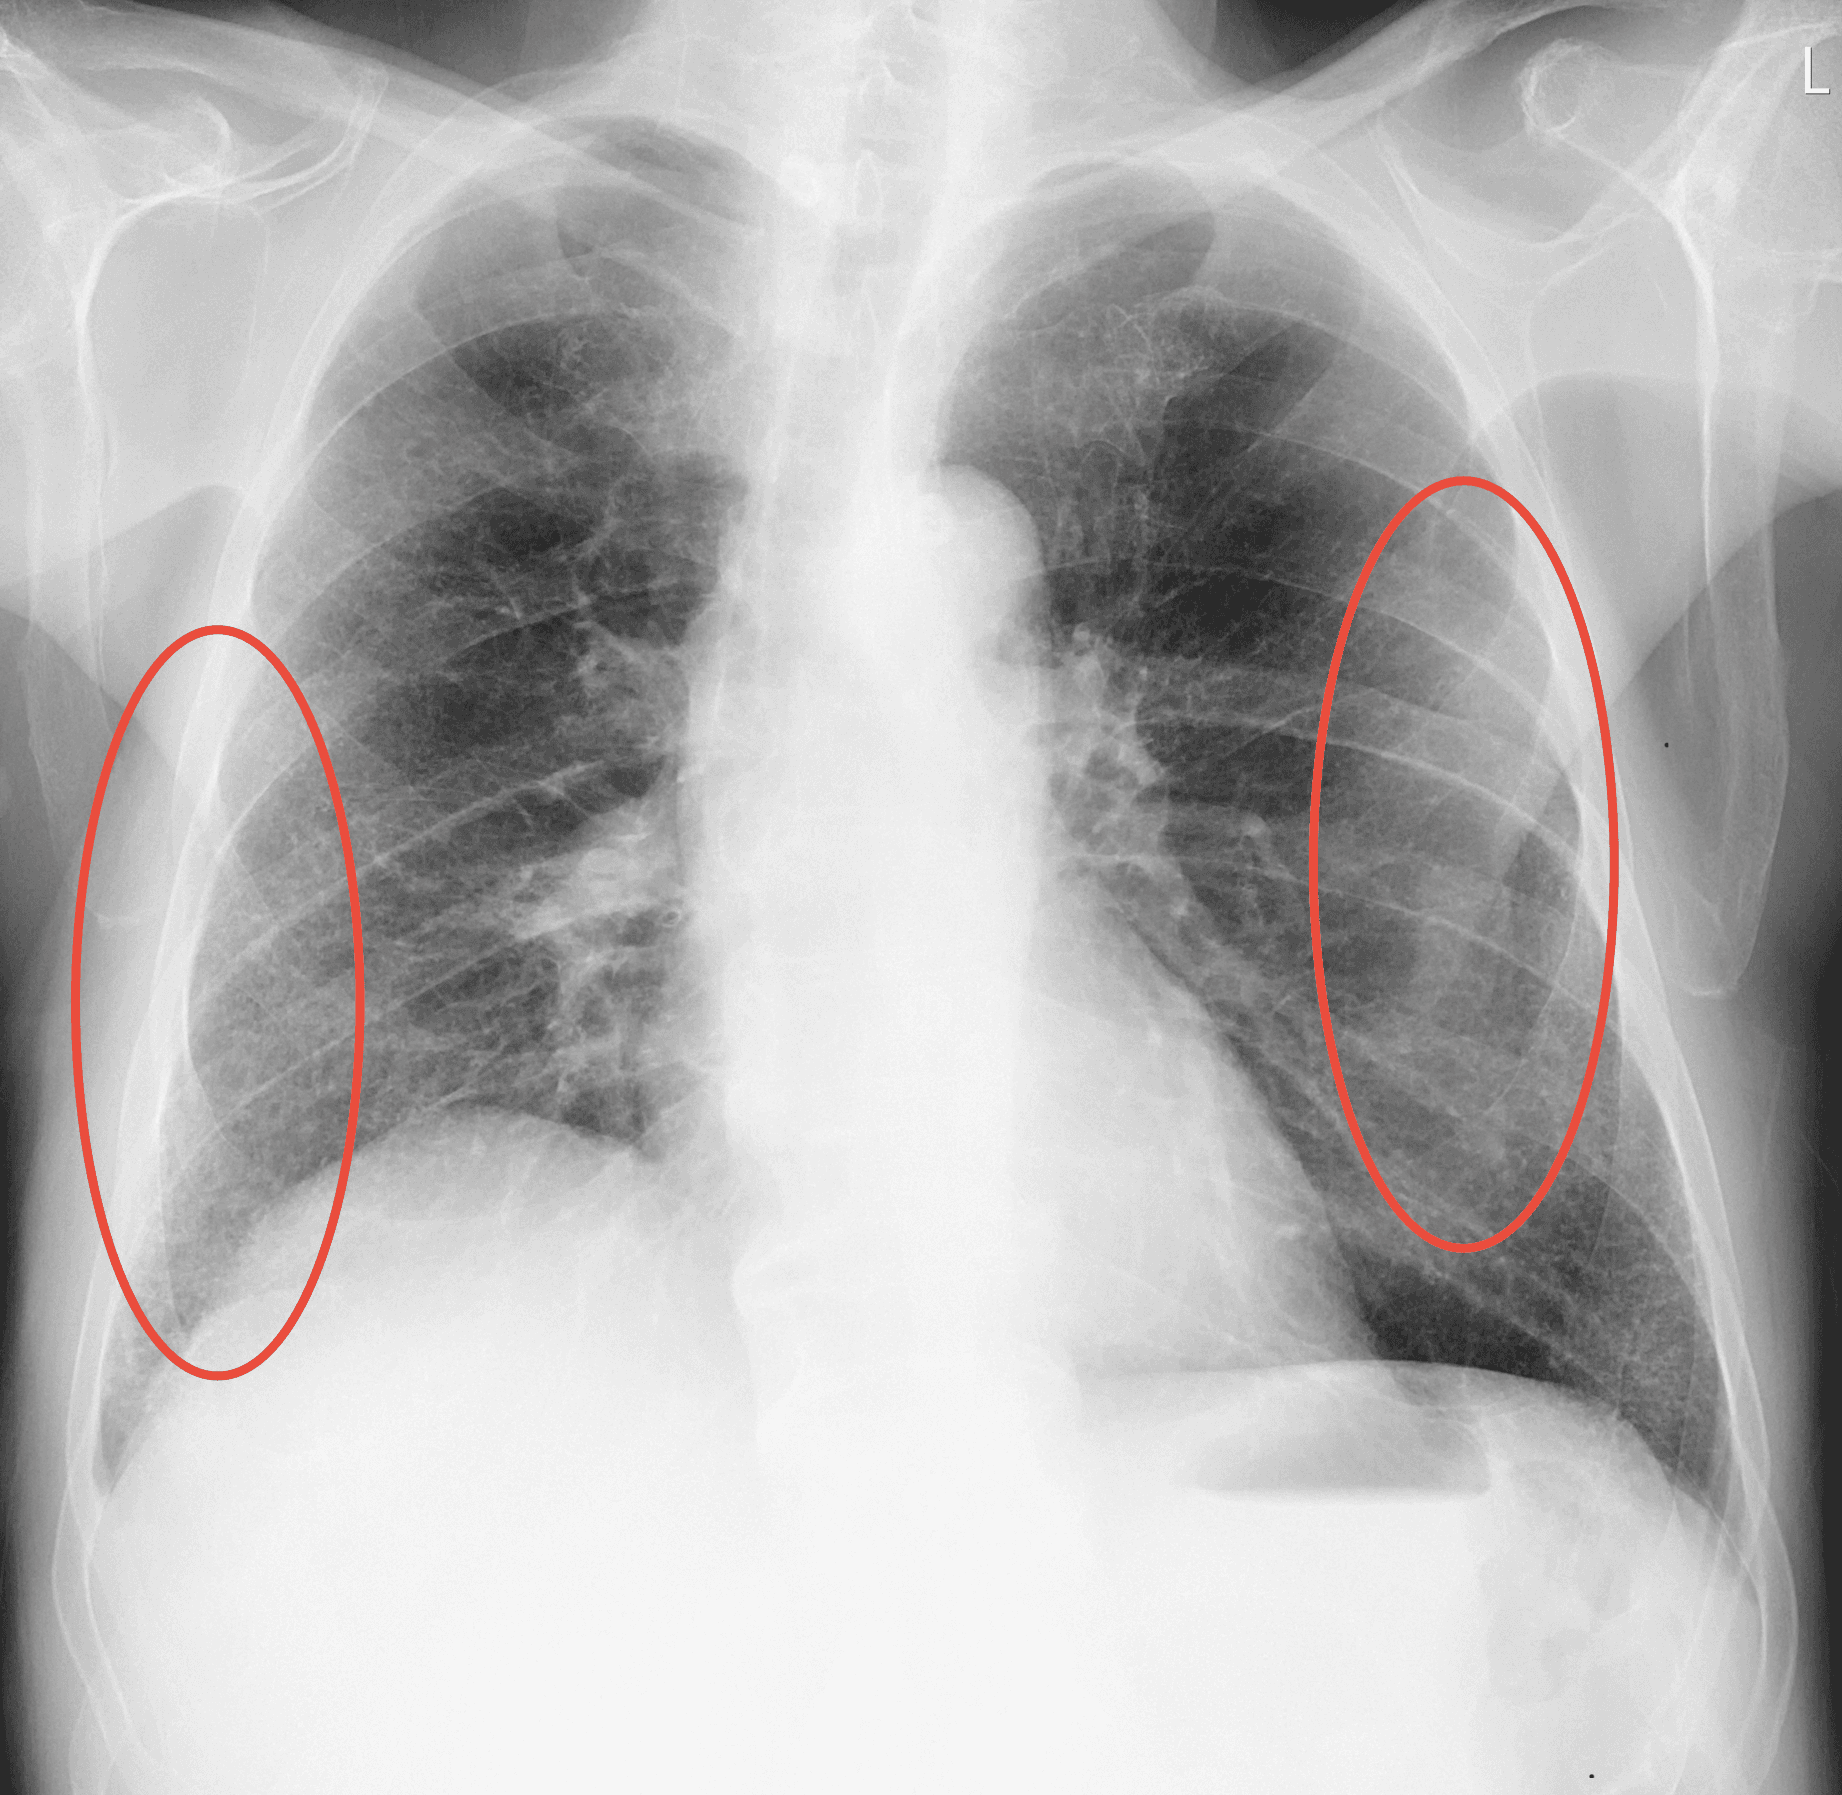

98% certainty

Medusa detected Emphysema in the lungs